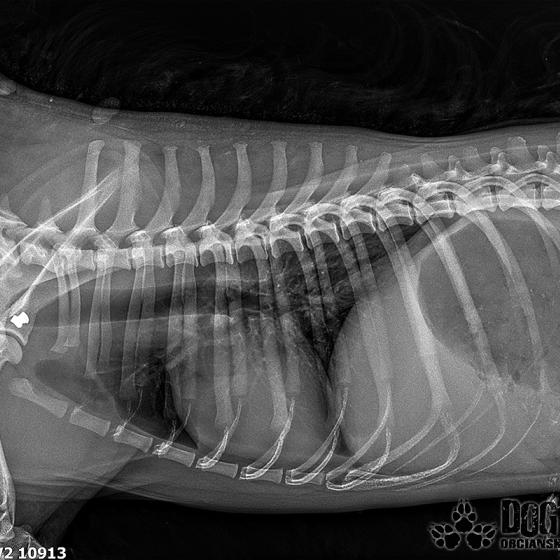

Vianoce nám klopú na dvere a mali by to byť sviatky radosti a pokoja. No u nás nebudú a pre malého Jamesa už vôbec nie. Malého Jamesa sme prijali s mnohonásobnými fraktúrami panvy. Presnejšie, s obojstrannou iliosakrálnou luxáciou/fraktúrou, viacnásobnou fraktúrou panvy, vrátane fraktúry kranialneho acetabula obojstranne. Áno, znie to hrozivo a keď si pozriete snímky z RTG, bude to ešte hrozivejšie (ďalšie snímky ešte doplníme).

Čakali ho teda štyri, veľmi náročné ortopedické operácie, takže sa musel trocha posilniť. Do starostlivosti si ho vzala MVDr. Panyi Terzieva a 17.11. mohol absolvovať prvú operáciu. V "prvom kole" krpec zvládal anestézu tak dobre, že sa rovno mohli spojiť dve operácie a tak sa celá ľavá strana dala do poriadku. Zostal samozrejme naďalej hospitalizovaný. Ďalší zákrok sa naplánoval na 20.11. a našťastie opäť všetko prebehlo hladko, a zoperovala sa celá pravá strana(nechceme sa dlho rozpisovať, prikladáme lekársku správu). James bol prepustený 24.11. ako chodiaci pacient a bez problémov ovládal aj vylučovanie! Je to priam zázrak, za ktorý opäť vďačíme MVDr. Vatolíkovi a jeho teamu.